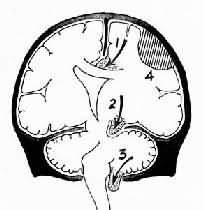

脑疝模式图

图16-6 脑疝模式图

1.扣带回疝;2.海马钩回疝;3.小脑扁桃体疝;4.硬膜外血肿